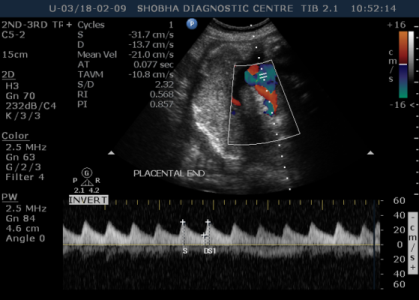

DOPPLER SONOGRAPHY / BIOPHYSICAL PROFILE

- Doppler Sonography gives information about blood circulation of the fetus.